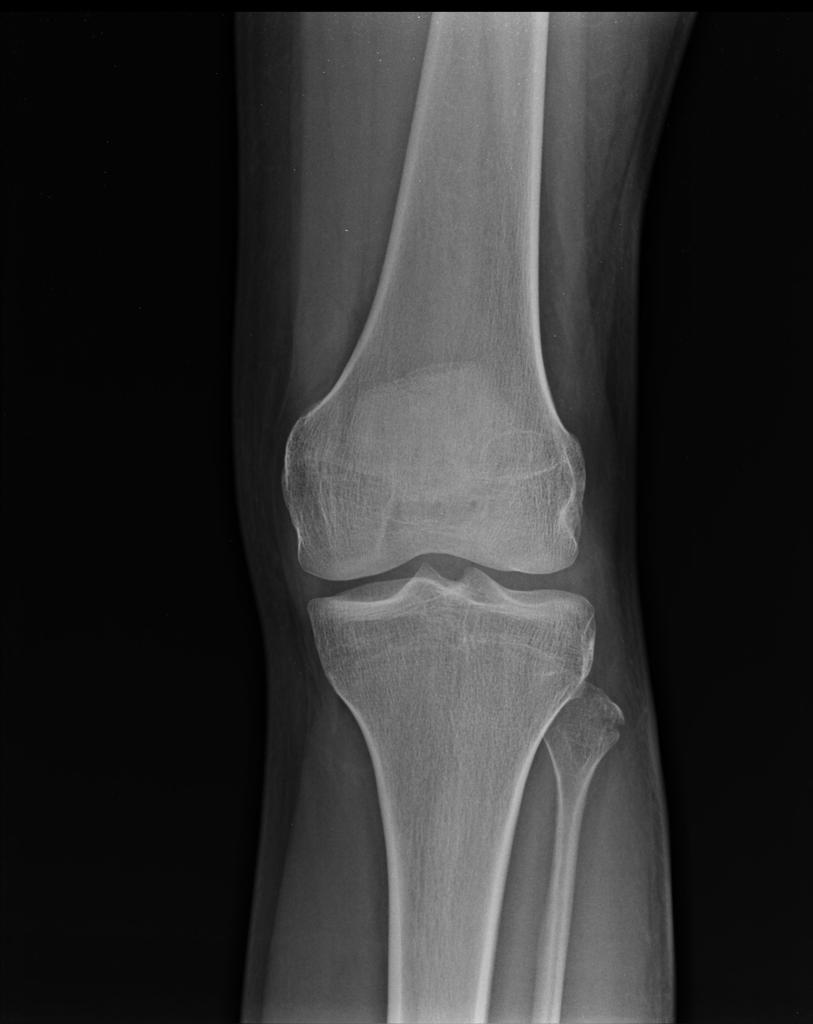

Example 1

Take a look at the following example. Let us go through how we would systematically analyse this and the diagnosis.

Analysis and Diagnosis

D – This is a … X-Ray taken on ….., of the following patient….. Is there a previous X-ray to compare to

R – Commenting first on the quality, it is not rotated, there is adequate field of view, the projection is AP and lateral and it is adequately exposed as I can see the bones clearly

“On initial inspection, there appears to be a fracture of the head of the fibula, but I will proceed to go through it systematically.”

B – Looking at the bones first, there is a fracture in the fibular head. It is a closed, simple, transverse fracture. There is no angulation of the distal segment compared to the proximal, no translation, rotation or shortening. There are no other fractures.

There are no obvious dislocations and the no abnormality in the texture of the bones

D – There are no degenerative changes in the joint spaces

E – There are no other man-made objects or signs of orthopaedic surgery.

In summary, this film shows a fracture of fibular head which is undisplaced.

Diagnosis

Fibular Head Fracture

Image 1: Patel, M. Fibular head fracture. Case study, Radiopaedia.org. https://doi.org/10.53347/rID-19493